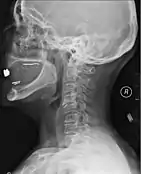

| MRI of a fractured and dislocated cervical vertebra (C4) in the neck that is compressing the spinal cord | |